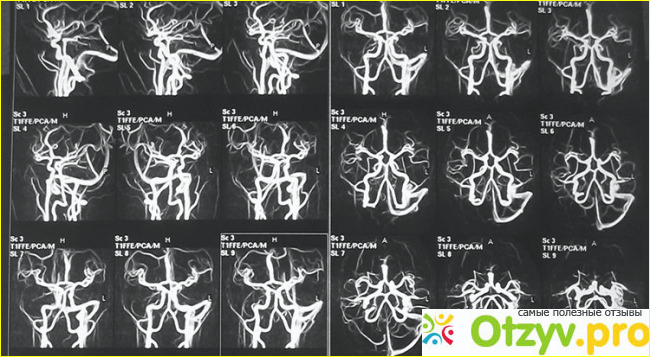

Но дуплексное сканирование не видит сквозь череп, как например, УЗДГ, но УЗДГ не видит сами сосуды. и чтобы разузнать их анатомию и уточнить наличие опасных сосудистых аномалий, например, аневризм, то здесь уже нужно МРТ сосудов головного мозга - с контрастом или нет. Раньше, когда не было МРТ, то делали просто контрастную ангиографию, когда после введения контрастного вещества в сосуды головного мозга делали рентген черепа. Это более дешевый метод, чем МРТ, поэтому его до сих пор делают.

5. МРТ сосудов головного мозга, бесконтрастное и контрастное